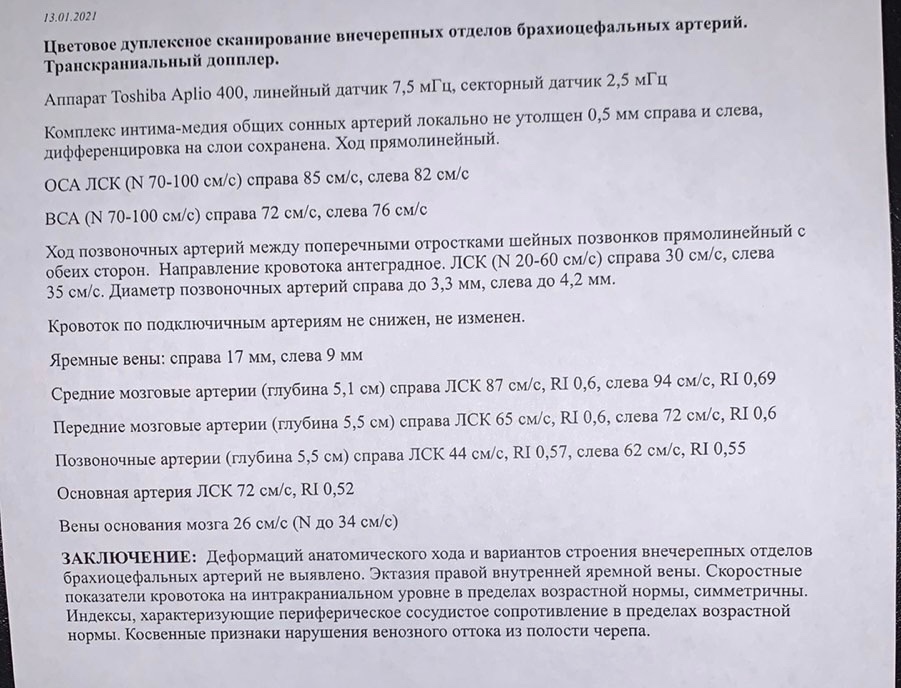

Анатомия внутренней яремной вены: КТ изображения